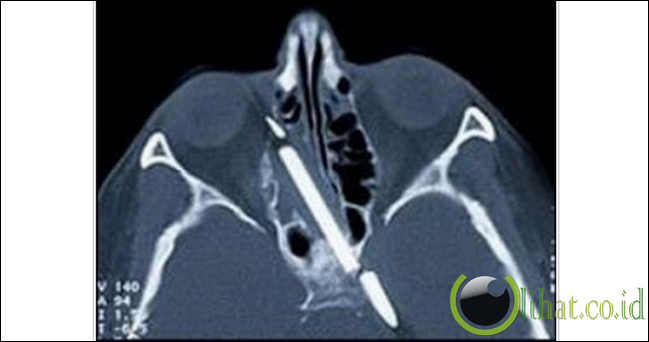

4. Pensil dalam kepala

[lihat.co.id] - Setelah menderita sakit kepala berat yang mengakibatkan terus mimisan selama 55 tahun, Margaret Wegner menjalani operasi pada bulan Agustus 2007. Saat inilah pensil sepanjang 3 inci akhirnya dikeluarkan dari kepalanya.

Uniknya, para dokter sebenarnya sudah mengetahui keberadaan pensil tersebut bersarang dalam kepala Wegner selama lima puluh tahun. Namun, selama itu pula dokter menunggu saat yang tepat. Dulu teknologi belum memungkinkan untuk operasi dan takut merusak kepala Wegner.

Untuk diketahui, Wegner mengalami kecelakaan saat berusuia 4 tahun dan menyebabkan sebatang pensil masuk ke dalam kepalanya.